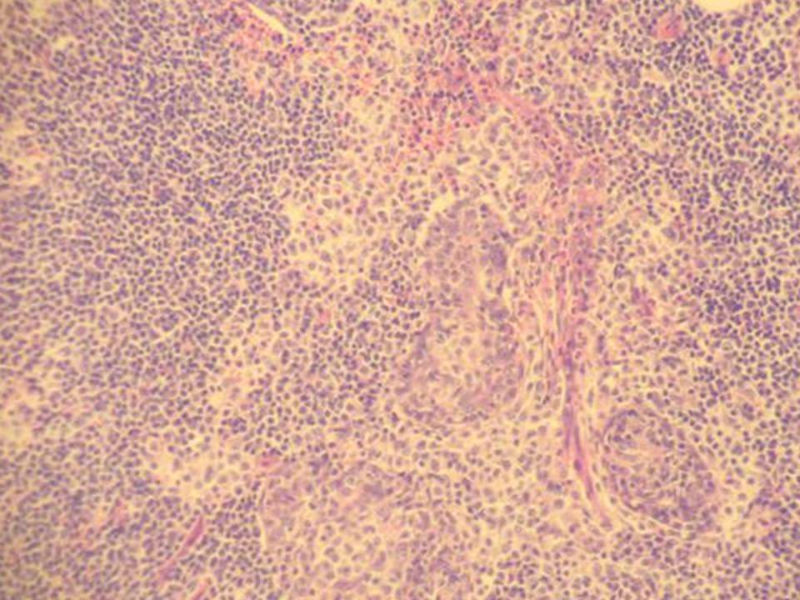

腮腺肿物:良性淋巴上皮病变(Mikulicz病)

女,71岁,腮腺肿物,临床诊断混合瘤。